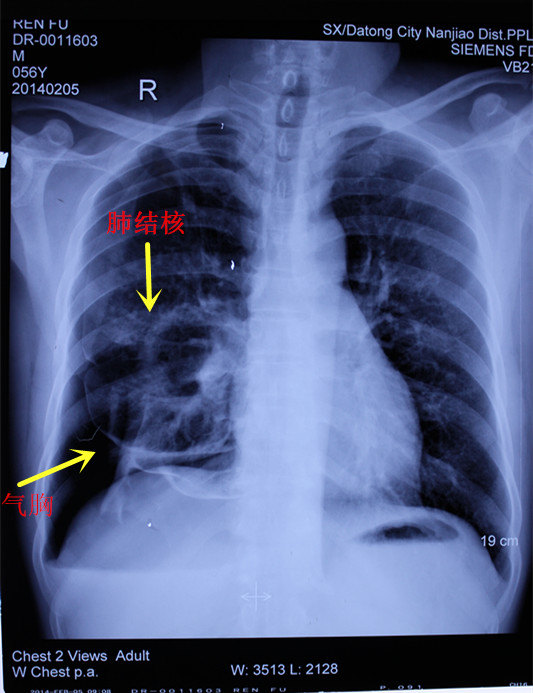

我是一名患有空洞型肺结核的患者,这是一个让人倍感焦虑和挣扎的疾病。空洞型肺结核是一种严重的肺结核病变,治疗过程漫长而痛苦,闭合时间也因人而异。

闭合的时间因人而异,有的患者可能需要几个月,有的甚至可能需要一年以上。但无论闭合时间长短,我相信只要坚持治疗,配合医生的建议,一定会迎来康复的曙光。